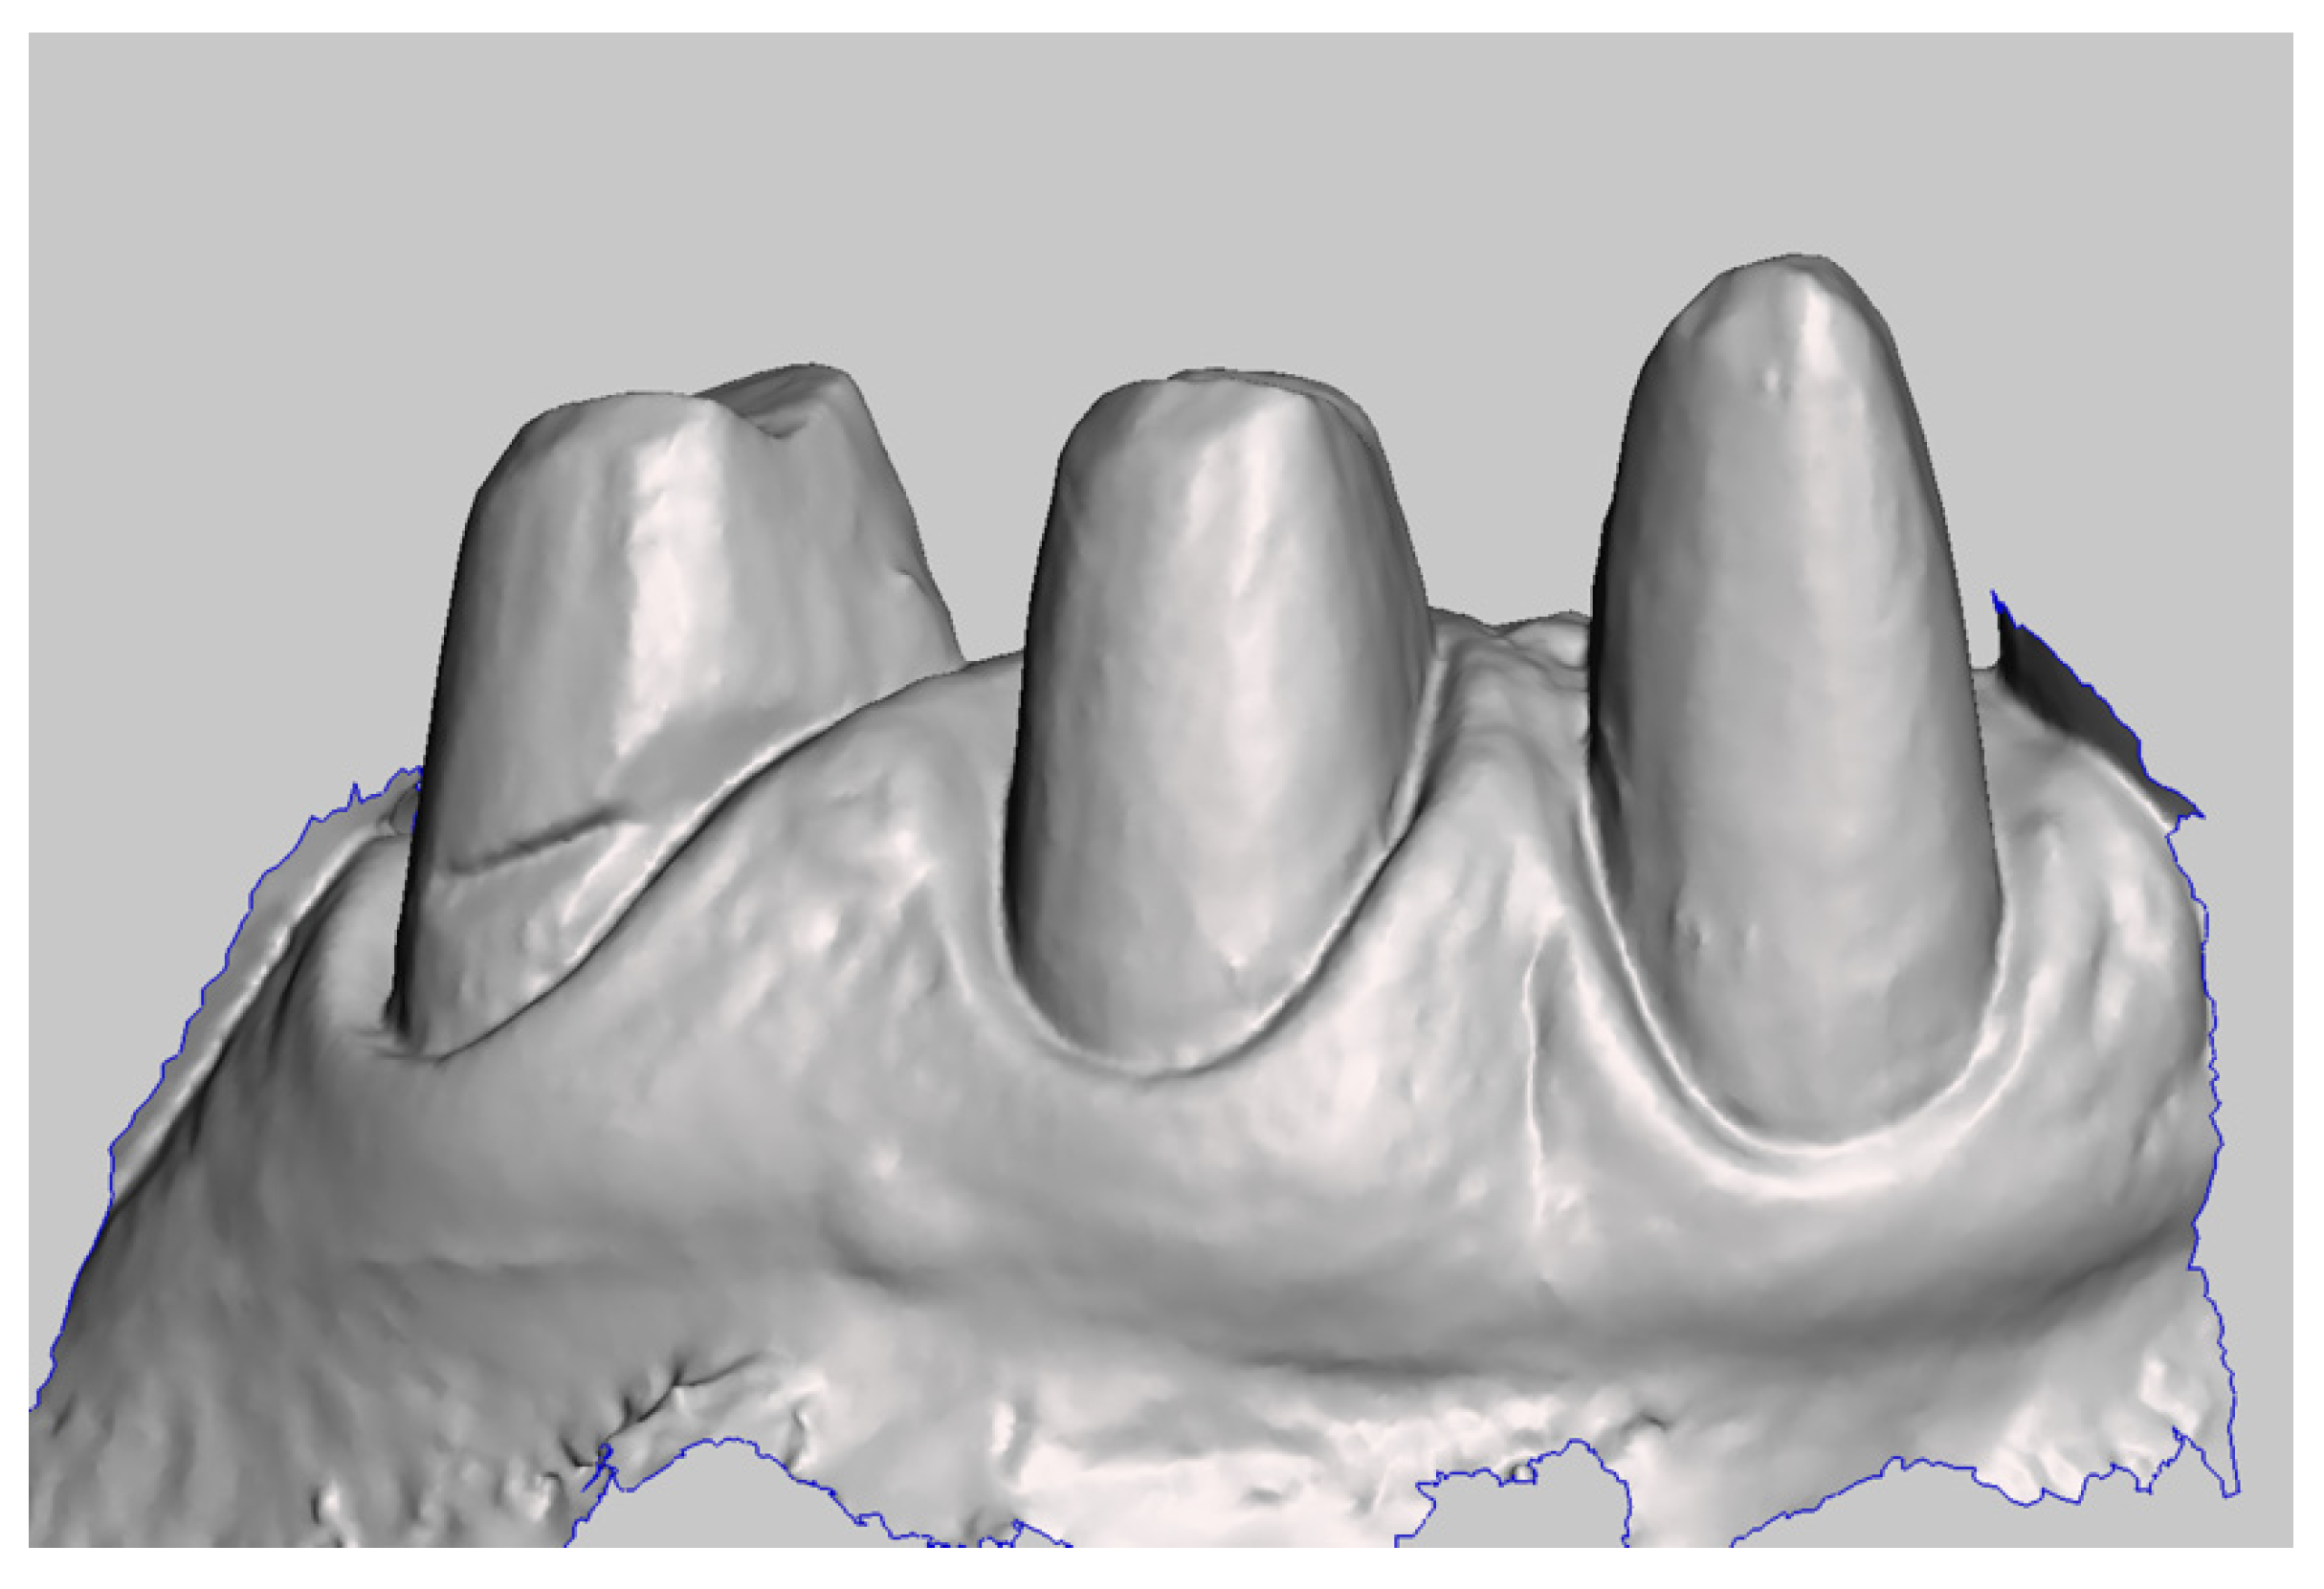

The master model was obtained by integrating two intraoral digital impressions (Figure 4), plus a scan of the temporary crowns using a Carestream CS3600 (Carestream Dental, Atlanta, GA, USA). The first impression scans the abutments, without retractor cords, following the recommended scanning protocol (both arches plus intercuspidal position). Next, an impression with the provisional restoration in place was taken. Subsequently, temporary crowns were scanned extraorally, acquiring their inner and outer margins (Figure 5). The resulting STL files were processed to produce a digital master model in which the data of the finish line of the abutments and of the surrounding tissues were derived from the temporary crowns. The workflow was performed using MeshMixer (Autodesk, Mill Valley, CA, USA) and Exocad (Align Technology, San Jose, CA, USA) (Figure 6).

Figure 4.

Digital impression of the abutments.